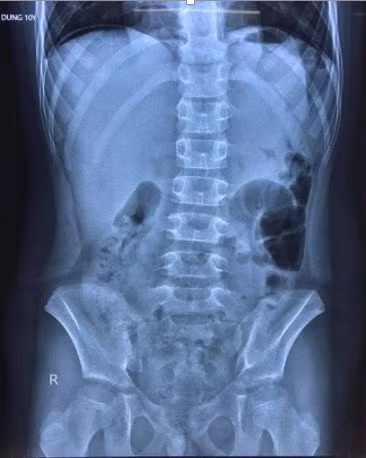

Hình ảnh chụp X-quang cho thấy bệnh nhi có liềm hơi dưới vòm hoành 2 bên, bác sĩ nghi thủng tạng rỗng. Ảnh: Bệnh viện Trẻ em Hải Phòng cung cấp.

Theo hình ảnh chụp X-quang, bệnh nhi có liềm hơi dưới vòm hoành 2 bên. Tại Bệnh viện Trẻ em, bé được chẩn đoán bị viêm phúc mạc do thủng dạ dày/mắc COVID-19.